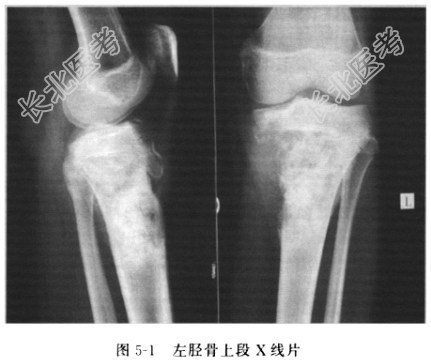

- [材料题] 患者男性,27岁,因“左下肢肿胀,疼痛1个月”入院。左下肢肿胀,疼痛1个月伴有发热,消瘦4kg,无外伤史。门诊下肢X线片(图5-1)示:左胫骨上端浸润性骨破坏,骨皮质不连续,可见骨膜反应及软组织肿块影,考虑骨肉瘤。查体:左小腿上段5cm×6cm×3cm肿物,质地硬、血运丰富、皮温增高、皮肤发红、静脉曲张。实验室检查,血碱性磷酸酶增高。X线检查示骨性破坏,界限不清楚,Codman三角、日照征。初步诊断:骨肿瘤。肿物穿刺活检示骨肉瘤,肿瘤细胞中高度分化。碱性磷酸酶升高,胸部X线片、腹部B超、骨扫描未见其他部位转移,肿瘤标志物正常。